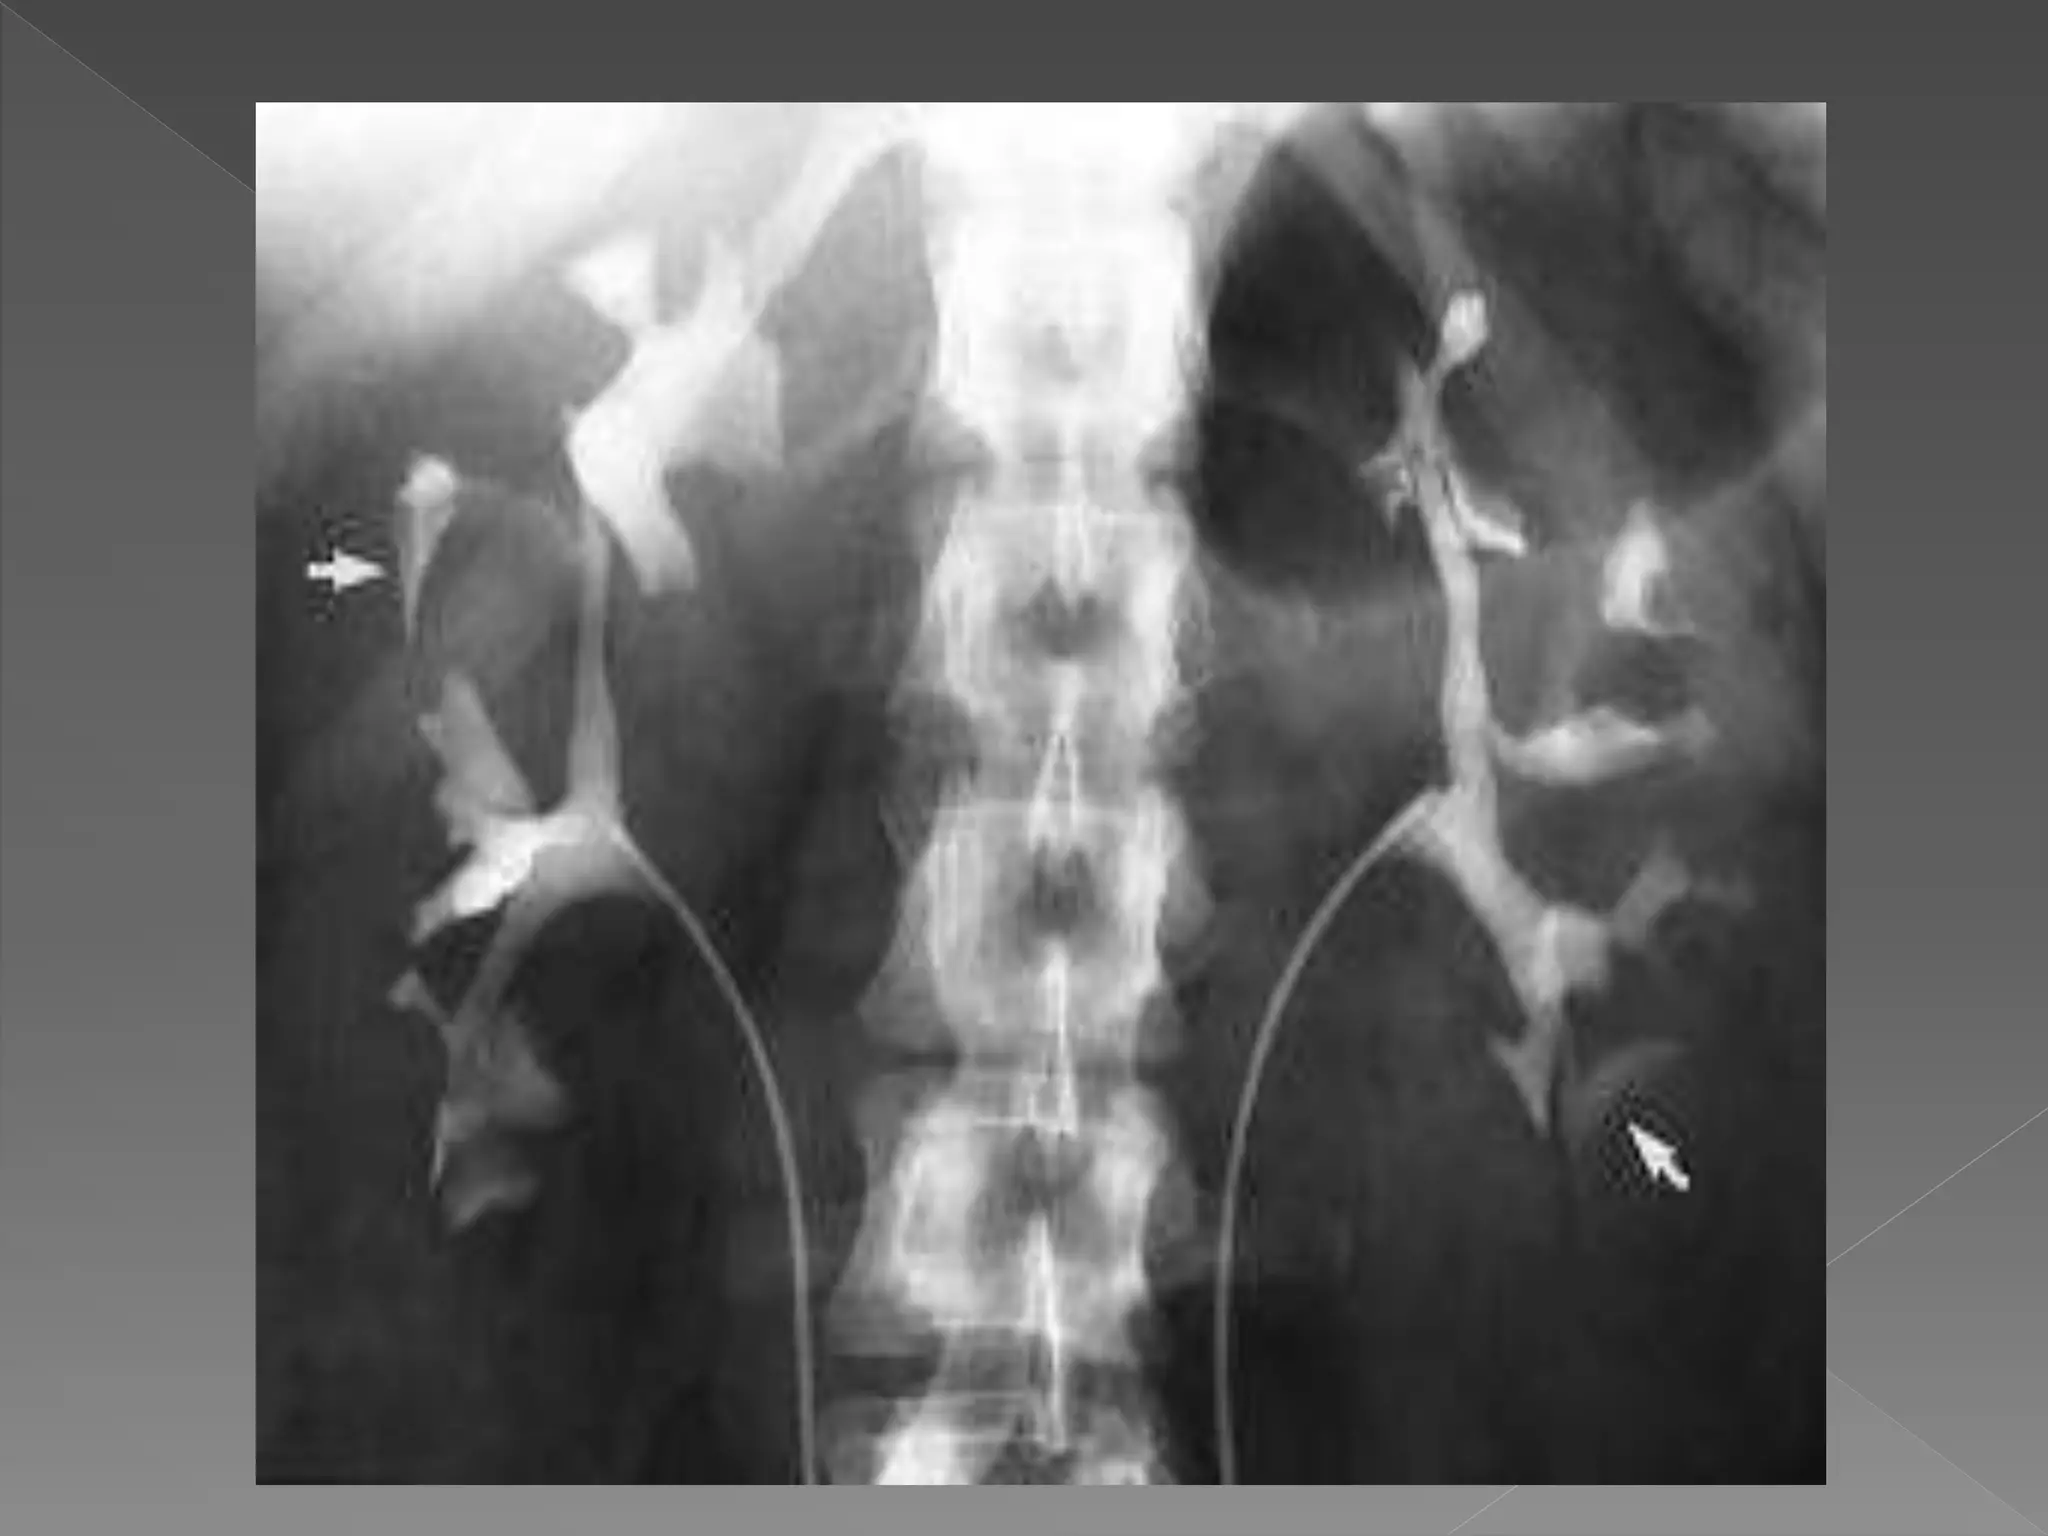

 In patientwith strong suspicion of ureteric calculi omit all films after contrast until a full length film is performed at 15 mins.  Patients with proven ureteric calculus for follow up IVU there should be a full length plain film & 15 mins post contrast film